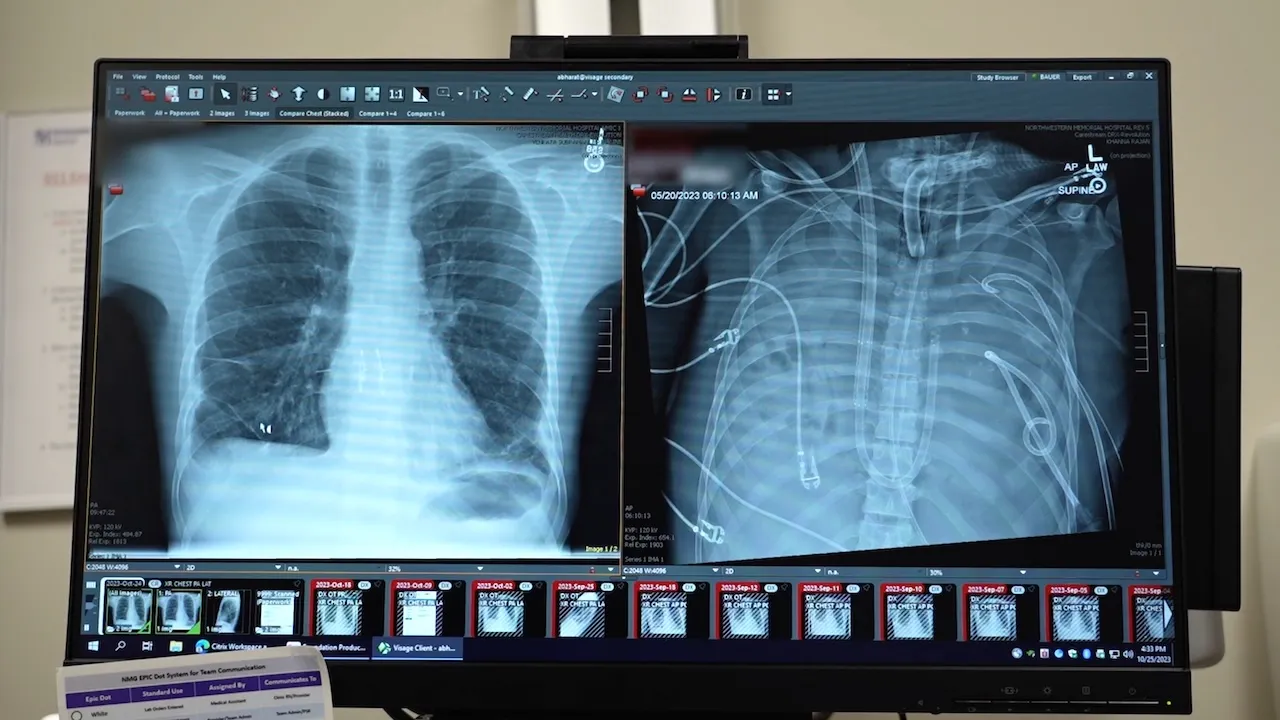

In a groundbreaking medical achievement, surgeons at Northwestern Medicine in Chicago successfully kept a 33-year-old patient alive for 48 hours after removing both of his lungs. The Missouri resident, whose name has not been disclosed, was initially transported to Northwestern Memorial Hospital in spring 2023 with severe lung failure resulting from a flu infection.

The patient’s condition rapidly deteriorated into severe pneumonia and sepsis, causing his heart to stop and requiring CPR, according to the hospital’s press release. Dr. Ankit Bharat, chief of thoracic surgery and executive director of the Northwestern Medicine Canning Thoracic Institute, explained the severity of the situation.

The medical team faced a critical dilemma: the infected lungs needed to be removed immediately to prevent the spread of the life-threatening infection, but doing so posed an extreme risk of immediate heart failure.

“The lungs act as a ‘shock absorber’ for the right side of the heart; when you remove them, the heart pumps against high resistance and can fail instantly,” Dr. Bharat explained. “Another critical danger is that without blood flowing from the lungs to the left heart, the left heart chambers can collapse or form deadly clots.”

To overcome these challenges, the surgical team designed an innovative “total artificial lung system” (TAL) that could temporarily take over the vital functions of the lungs while the patient awaited a transplant. This system maintained blood oxygenation, removed carbon dioxide, and preserved critical blood flow to the heart.

The details of this remarkable case were published last week in the Cell Press journal Med. The study included a molecular analysis of the removed lungs, revealing extensive scarring and tissue damage. This finding supports the notion that in some severe cases of acute respiratory distress syndrome, transplantation may be the only viable treatment option.